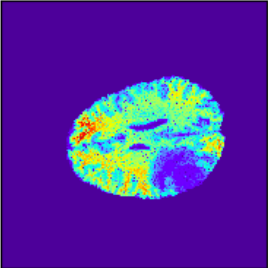

(e) Uncertainty

(j) Uncertainty

Figure 3: Intra and Inter modality MR registration. Time taken: 0.21 sec

To illustrate the performance of the proposed technique for clinical applications, MR images were chosen. The performance of the technique was tested by registering multi-modal MR image pairs. In a clinical setup, it is common practice to register images or volumes acquired from different imaging modalities or MR sequences. Figure 3 illustrates the degree of overlap between moving images (a) T2 and (f) T1 weighted sequence on fixed images (b) T2 and (g) T2 weighted sequence respectively. It was observed using the registration proposed in this manuscript, the dice score improved from 0.44 (prior to registration) to 0.91 (post registration) for multimodal sequences. On the BraTs data, figure 4 (a-d) illustrates the performance of our method based on other metrics such as Dice, SSMI, MI, and MSE respectively. As the key points were generated by utilizing only the feature maps of the initial two layer of the network, the spatial dimension of the data has little impact on the performance. Unlike other CNN based technique which considers the entire image for estimating the transformation parameters, our method requires CoMs which reduces the dimensionality from (m ×\times n ×\times n) to (m ×\times 2), where m denotes the number of feature maps and n is the pixel dimension of the feature map. This aids in lowering execution time drastically. The proposed pipeline also consists of an uncertainty estimator. uncertainty maps illustrated in all the above examples show the region of higher variance in registration, which in turn suggests surgeons/ observers to make better decisions. Pixel region with red color indicates the larger variance region while blue indicated low variance region. For example in figure 3 (e) shows that the central region of the brain has higher pixel-wise variance as compared to the outer part of the brain. The performance of the algorithm on volumes on the same modality is illustrated in figure 3 (a-e)